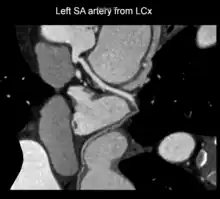

A left S-shaped sinoatrial artery, originating from the proximal left circumflex or LCx artery, has been described as a common variant in approximately 10% of human hearts.[5] This artery is larger than normal and supplies a good part of the left atrium, but also right-sided structures like part of the sinoatrial node and the atrioventricular nodal areas. In this variant, the artery courses in the sulcus between the left superior pulmonary vein and the left atrial appendage where it could be susceptible to injury during catheter or surgical ablation procedures on the left atrium, especially for atrial fibrillation ablation or open-heart cardiac surgery.